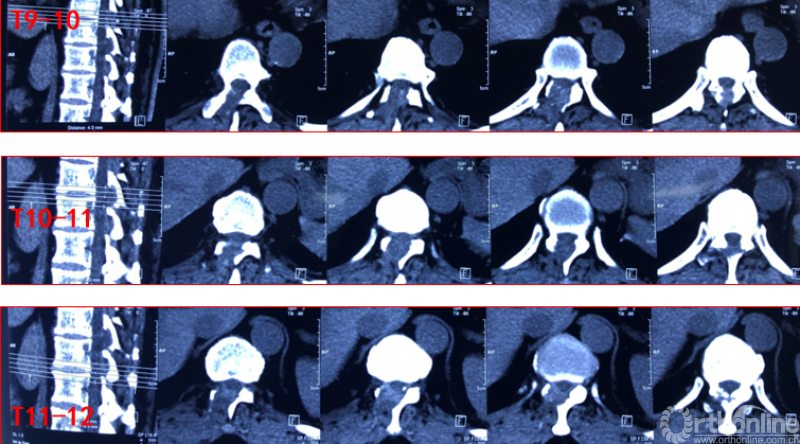

影像学资料

术中资料

同一侧一次两个节段减压,择期对侧进行两个节段减压,两侧腹侧减压范围可达到硬膜囊360度环形减压效果。术后复查硬膜囊环形减压效果。关节突关节破坏较多,需长期佩戴支具固定,保证术后脊柱稳定性。

术后复查资料